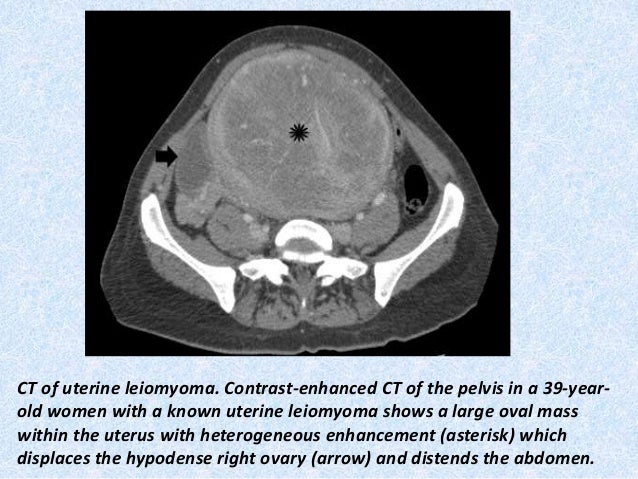

Second There is a heterogeneous subserosal uterine lesion measuring 8×6×6 Also a posterior hypoechoic uetrine lesion Small calcification in right ovaryUterus with 59*47*57 mm diameter is relatively normal in size, shape and echo texture No mass lesion is noted There is welldefined normalappearing endometrial 14 mm stripe There is more than 50 mm heterogeneous cystic component in right adnexa CT scan (a) showed large heterogeneous uterine mass measuring 145 × 154 × 13 cm compressing the bladder, adjacent bowel loops, and distal ureter MRI (b) showed the uterus is significantly enlarged with a mass lesion measuring approximately 16 × 11 cm presumed to be in the uterine myometrium